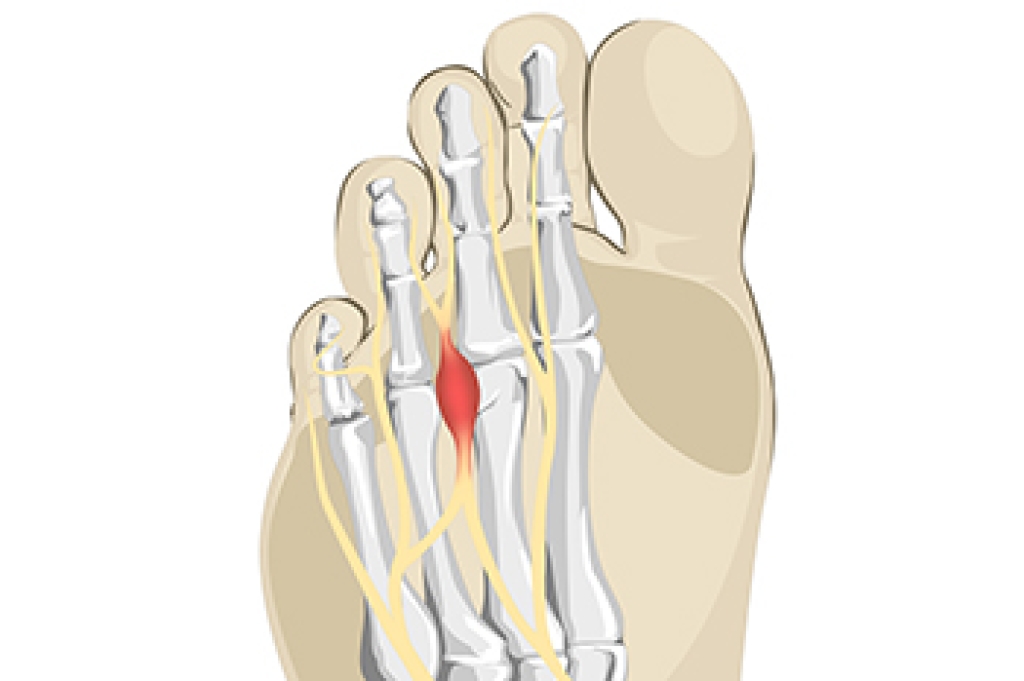

Morton’s neuroma is a painful condition that involves thickening of the tissue surrounding a nerve, most often between the third and fourth toes. It causes sharp, burning pain in the ball of the foot, tingling, or the feeling of a pebble in the shoe. Risk factors include wearing tight or high-heeled shoes, foot deformities like bunions or flat feet, and repetitive stress from running and other activities. Causes stem from nerve irritation or compression over time. A podiatrist can diagnose the condition through examination and imaging, provide custom orthotics, recommend footwear changes, and offer advanced treatment to relieve pain. If you have pain in this part of your foot, it is suggested that you consult a podiatrist who can provide an accurate diagnosis and treatment.

Morton’s Neuroma

Morton's neuroma is a painful foot condition that commonly affects the areas between the second and third or third and fourth toe, although other areas of the foot are also susceptible. Morton’s neuroma is caused by an inflamed nerve in the foot that is being squeezed and aggravated by surrounding bones.

Morton’s neuroma is a very treatable condition. Orthotics and shoe inserts can often be used to alleviate the pain on the forefront of the feet. In more severe cases, corticosteroids can also be prescribed. In order to figure out the best treatment for your neuroma, it’s recommended to seek the care of a podiatrist who can diagnose your condition and provide different treatment options.